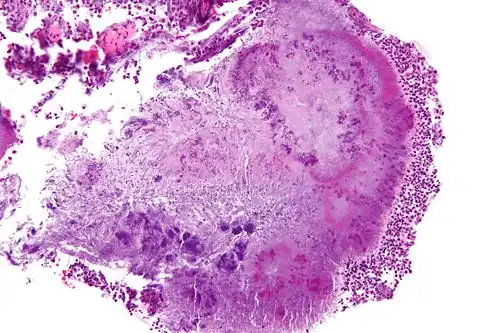

| High-magnification micrograph of a "sulfur" granule formed by Actinomyces in the mandible, H&E stain | |

To diagnose lumpy jaw, the fluids exuding from the bony lump or other abscesses are sampled or aspirated if the infection has not broken through the skin.[18] Tissue samples from the lesion can be examined by histopathology after being embedded in paraffin wax, cut into 4- to 5-mm sections, and stained with hemolysin and eosin stains.[17] The clubs could also be stained by carbol fuchsin with decolourisation by weak hydrochloric acid and counter-staining with methylene blue, Van Gieson's stain, or aniline gentian violet followed by treatment with alcohol.[20] A. bovis can be identified histologically by its basophilic colonies and club-shaped reaction product visible in neutrophilic granulomatous lesions.[17] The club-shapes, also called Spendore-Hoeppli proteins, seen on histological slides are the result of the bacteria being encased in a calcium-phosphate protein complex, as the host attempts to wall off the infection.[17] Another diagnostic feature is the presence of "sulfur" granules,[6] which is pathognomonic for actinomycosis.[17] These granules are small, yellow clumps of exudate that are visible to the naked eye with a similar appearance to grains of sulfur, and are mainly composed of bacterial filaments and host calcium phosphate.[17]